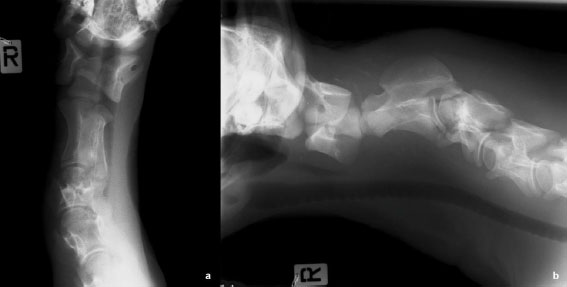

As the musculature of the cervical region was macroscopically deformed and presented increased stiffness, a radiographic examination was carried out before necropsy. Laterolateral and ventrodorsal radiographs of the cervical spine were carried out revealing atlantoaxial joint deviation, C2–C3 subluxation, C3 cranial vertebral body surface flattening, and multiple fracture lines in the cranial vertebral body of C3 (Fig. 1).

Fig. 1. (a) Ventrodorsal and (b) lateral left-right radiographs of the cranial cervical spine evidencing surrounding soft tissue edema, fracture of C3 cranial vertebral body (dislocated dorsally and with surface flattening), C2–C3 subluxation, and atlantoaxial joint deviation.